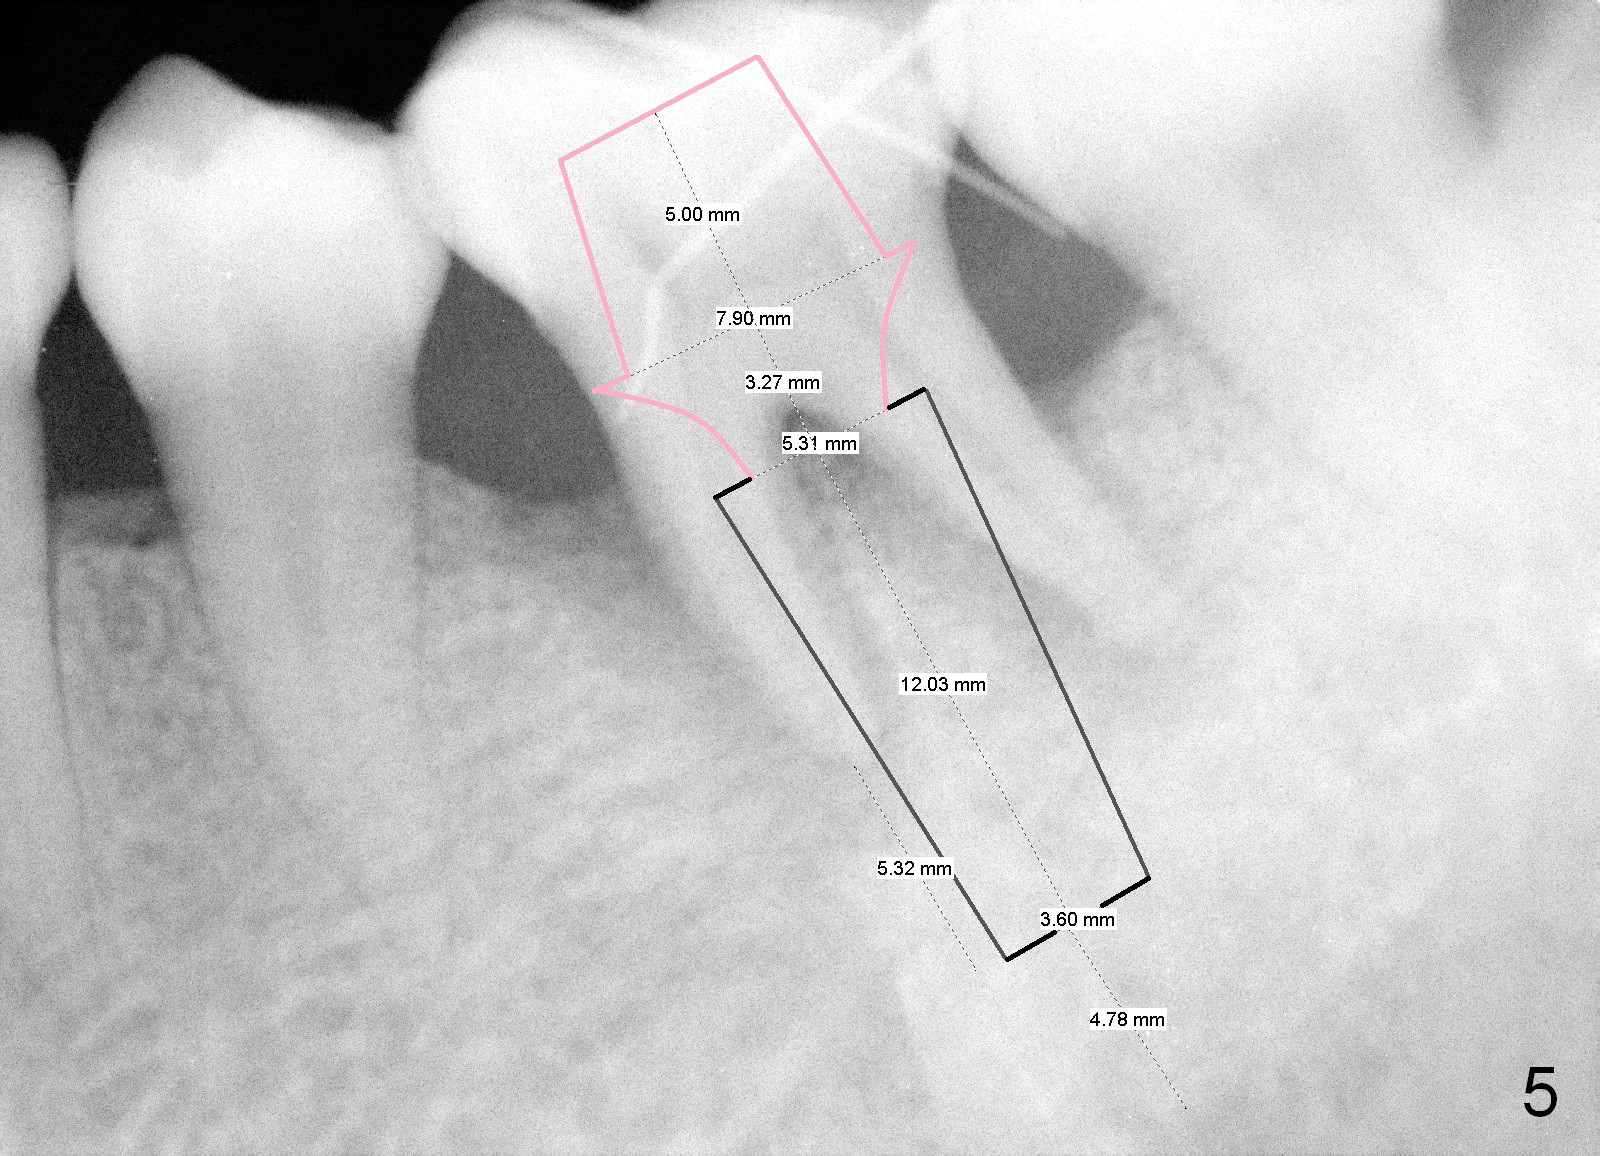

A 43-year-old lady has generalized moderate localized advanced chronic periodontits (Fig.1,2). In spite of 4 quadrant scaling & root planing, the tooth #19 develops 2 perio abscesses (Fig.4 with insertion of 2 guttae perchae); periodontal ligament spaces increases (compare Fig.2,4). It appears that the tooth is non salvageable and should be replaced with an immediate implant (Fig.5). The extraction socket will be treated with Metronidazole. A 2 mm pilot drill is used to start osteotomy in the septum (14 mm deep), followed by reamers until 3.5 mm. A 5x17 mm tap is placed to test stability. If the stability is high, place a 5.3x12 mm SM implant. If insertion torque is too high, use the corresponding drill before re-place the implant. Collagen dressing is placed in the peripheral and deep portion of the sockets, while bone graft in the top portion of the sockets (near implant threads). Use 1 or 2 amalgam carriers to deliver the graft lateral to the implant precisely so that a cover screw does not have to be placed. Next place a cemented abutment. If trajectory of the implant is correct, an abutment as large as 7.8x5(3) mm could be used (pink). Fabricate an immediate provisional. Do not over trim the margin of the provisional so that it can cover the socket completely.